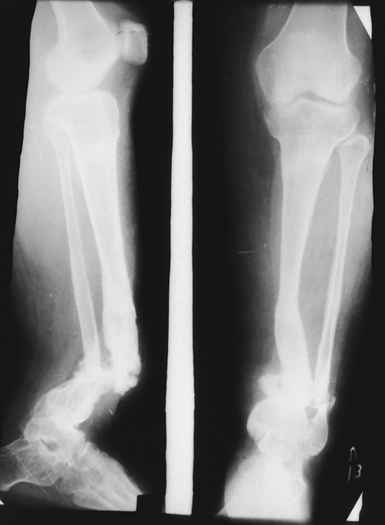

На первом этапе аппаратом Илизарова закрыто устранена деформация голени.

На втором этапе произведёно освежение краёв костных фрагментов б/б и м/б костей с приданием проксимальному фрагменту б/б кости впалой, а дистальному выпуклой формы, открытие канала проксимального фрагмента и погружной остеосинтез, а также остеотомия б/б кости в в/3 и м/б кости на границе с/3 и н/3 голени. Больной проводился одновременный бифокальный компрессионно-дистракционный остеосинтез. Достигнуто 11 см. удлинение и сращение ВПГ.

Срок лечения 11 месяцев. Наблюдение 2 года.